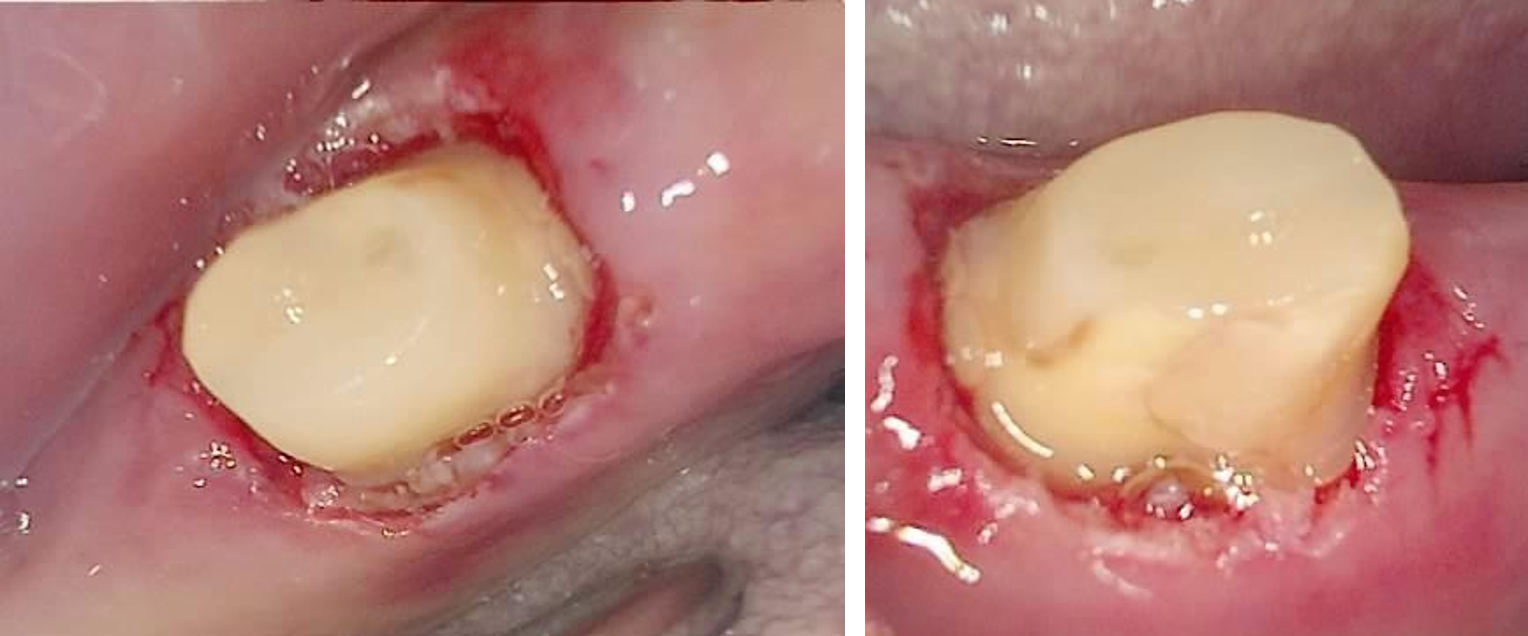

긴장되는 마음으로 크라운을 분리해보니, 헐...

냄새가 나는 크라운을 제거하니, 치아의 머리가 다 녹아있는 모습

치아의 머리가 사라졌다

치아의 머리가 싹 다 녹았다. 이래서 브릿지가 무서운 거다.

크라운 아래 치아가 저렇게 싹 녹아버렸지만,

옆의 크라운과 단단하게 연결되어 있으니 흔들림도 없고 별 불편함을 못 느끼고 계셨던 거다.